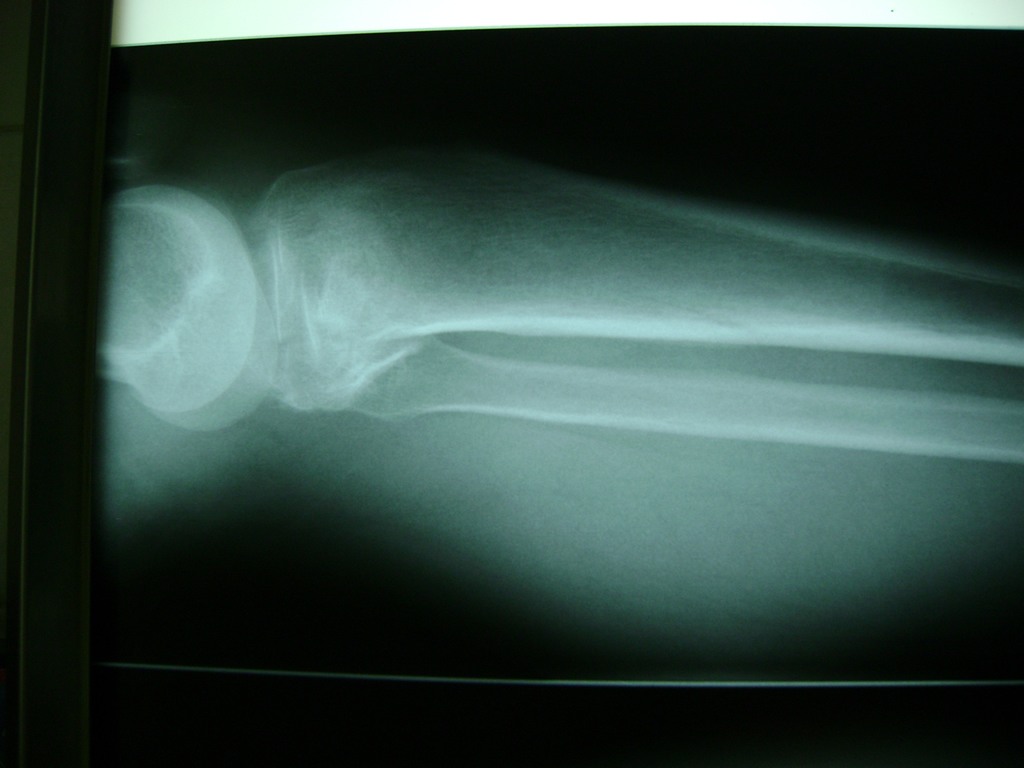

Fémur - Rodilla

La artroscopia de rodilla es un cirugía en el cual la estructura interna de la articulación es examinada ya sea para realizar un diagnostico o para realizar un tratamiento, este procedimiento se realiza utilizando un instrumento parecido a un pequeño tubo llamado artroscopio.